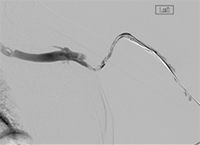

xray of occlusive thrombus extending into the iliac vein.

Occlusive thrombus extending into the iliac vein